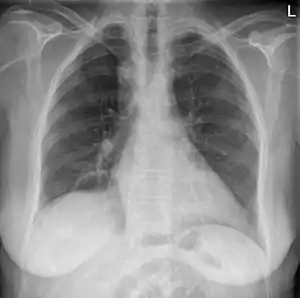

| Anterior-posterior chest radiograph showing a right-sided aortic arch |

After birth, a right-sided aortic arch is visualized on chest radiography, by the aortic knob (the prominent shadow of the aortic arch) that is located right from the sternum instead of left. Complex lesions are often assessed by MRI or CT.